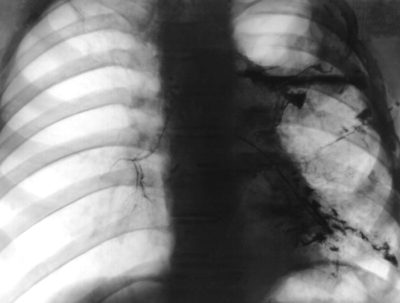

Анализ мокроты на микобактерии и цитологию; туберкулиновые пробы (при подозрении на туберкулезный плеврит); инструментальные исследования (рентгенография органов грудной клетки, КТ легких, плевральная пункция с исследованием жидкости, УЗИ плевральных полостей и сердца, ЭКГ, торакоцентез с биопсией, торакоскопия).